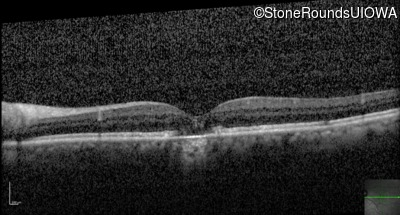

Optical Coherence Tomography - Right - 20/20 -2

Exemplar / OCT Stack

Optical Coherence Tomography - Left - 20/50